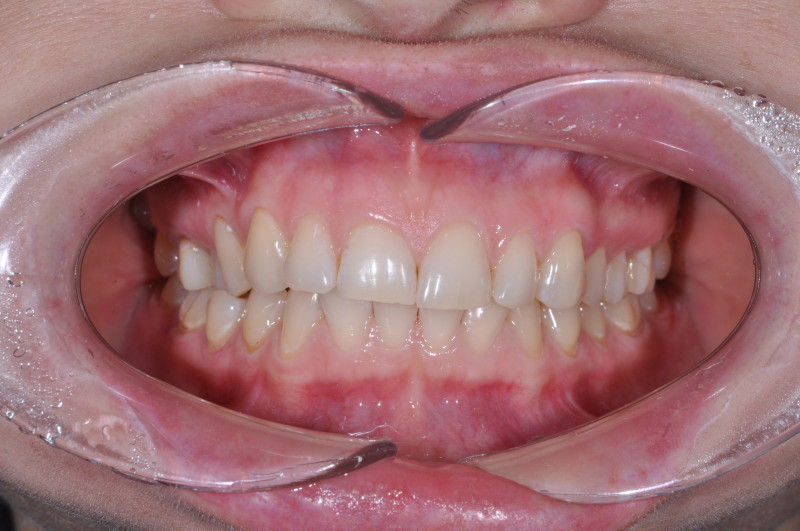

Установка сапфировых брекетов

Недоразвитие нижней челюсти, большой наклон передних зубов. Срок лечения 2 года. Сапфировые брекеты.

Доктор: Хачатрян Лариса Рубеновна